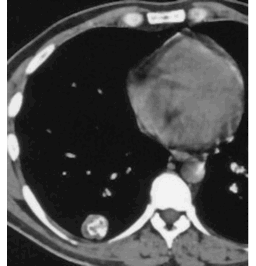

How would you describe the LUNG abnormality in each of these cases?

C